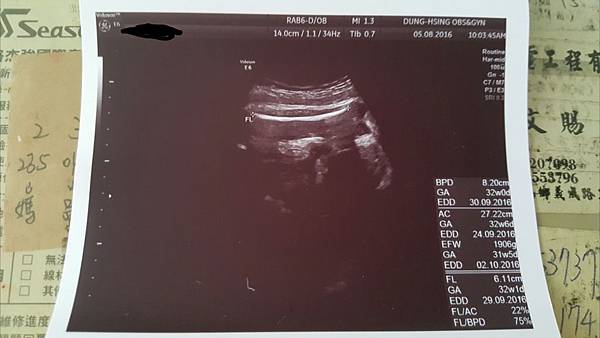

今天去照了4D超音波

主要是以嘗鮮為目的啦這機器跟高雄的產檢醫院滿類似的

順便看看寶寶到底長什麼樣子![]()

照片是她的腿骨測量右下角寫著重量1906g評估是32W.....還有點小隻表示我要繼續再吃養胎中藥

強而有力的心跳145下/分鐘不過技術人員說是148快接近男寶寶的心跳了

記得當初萱是140而已